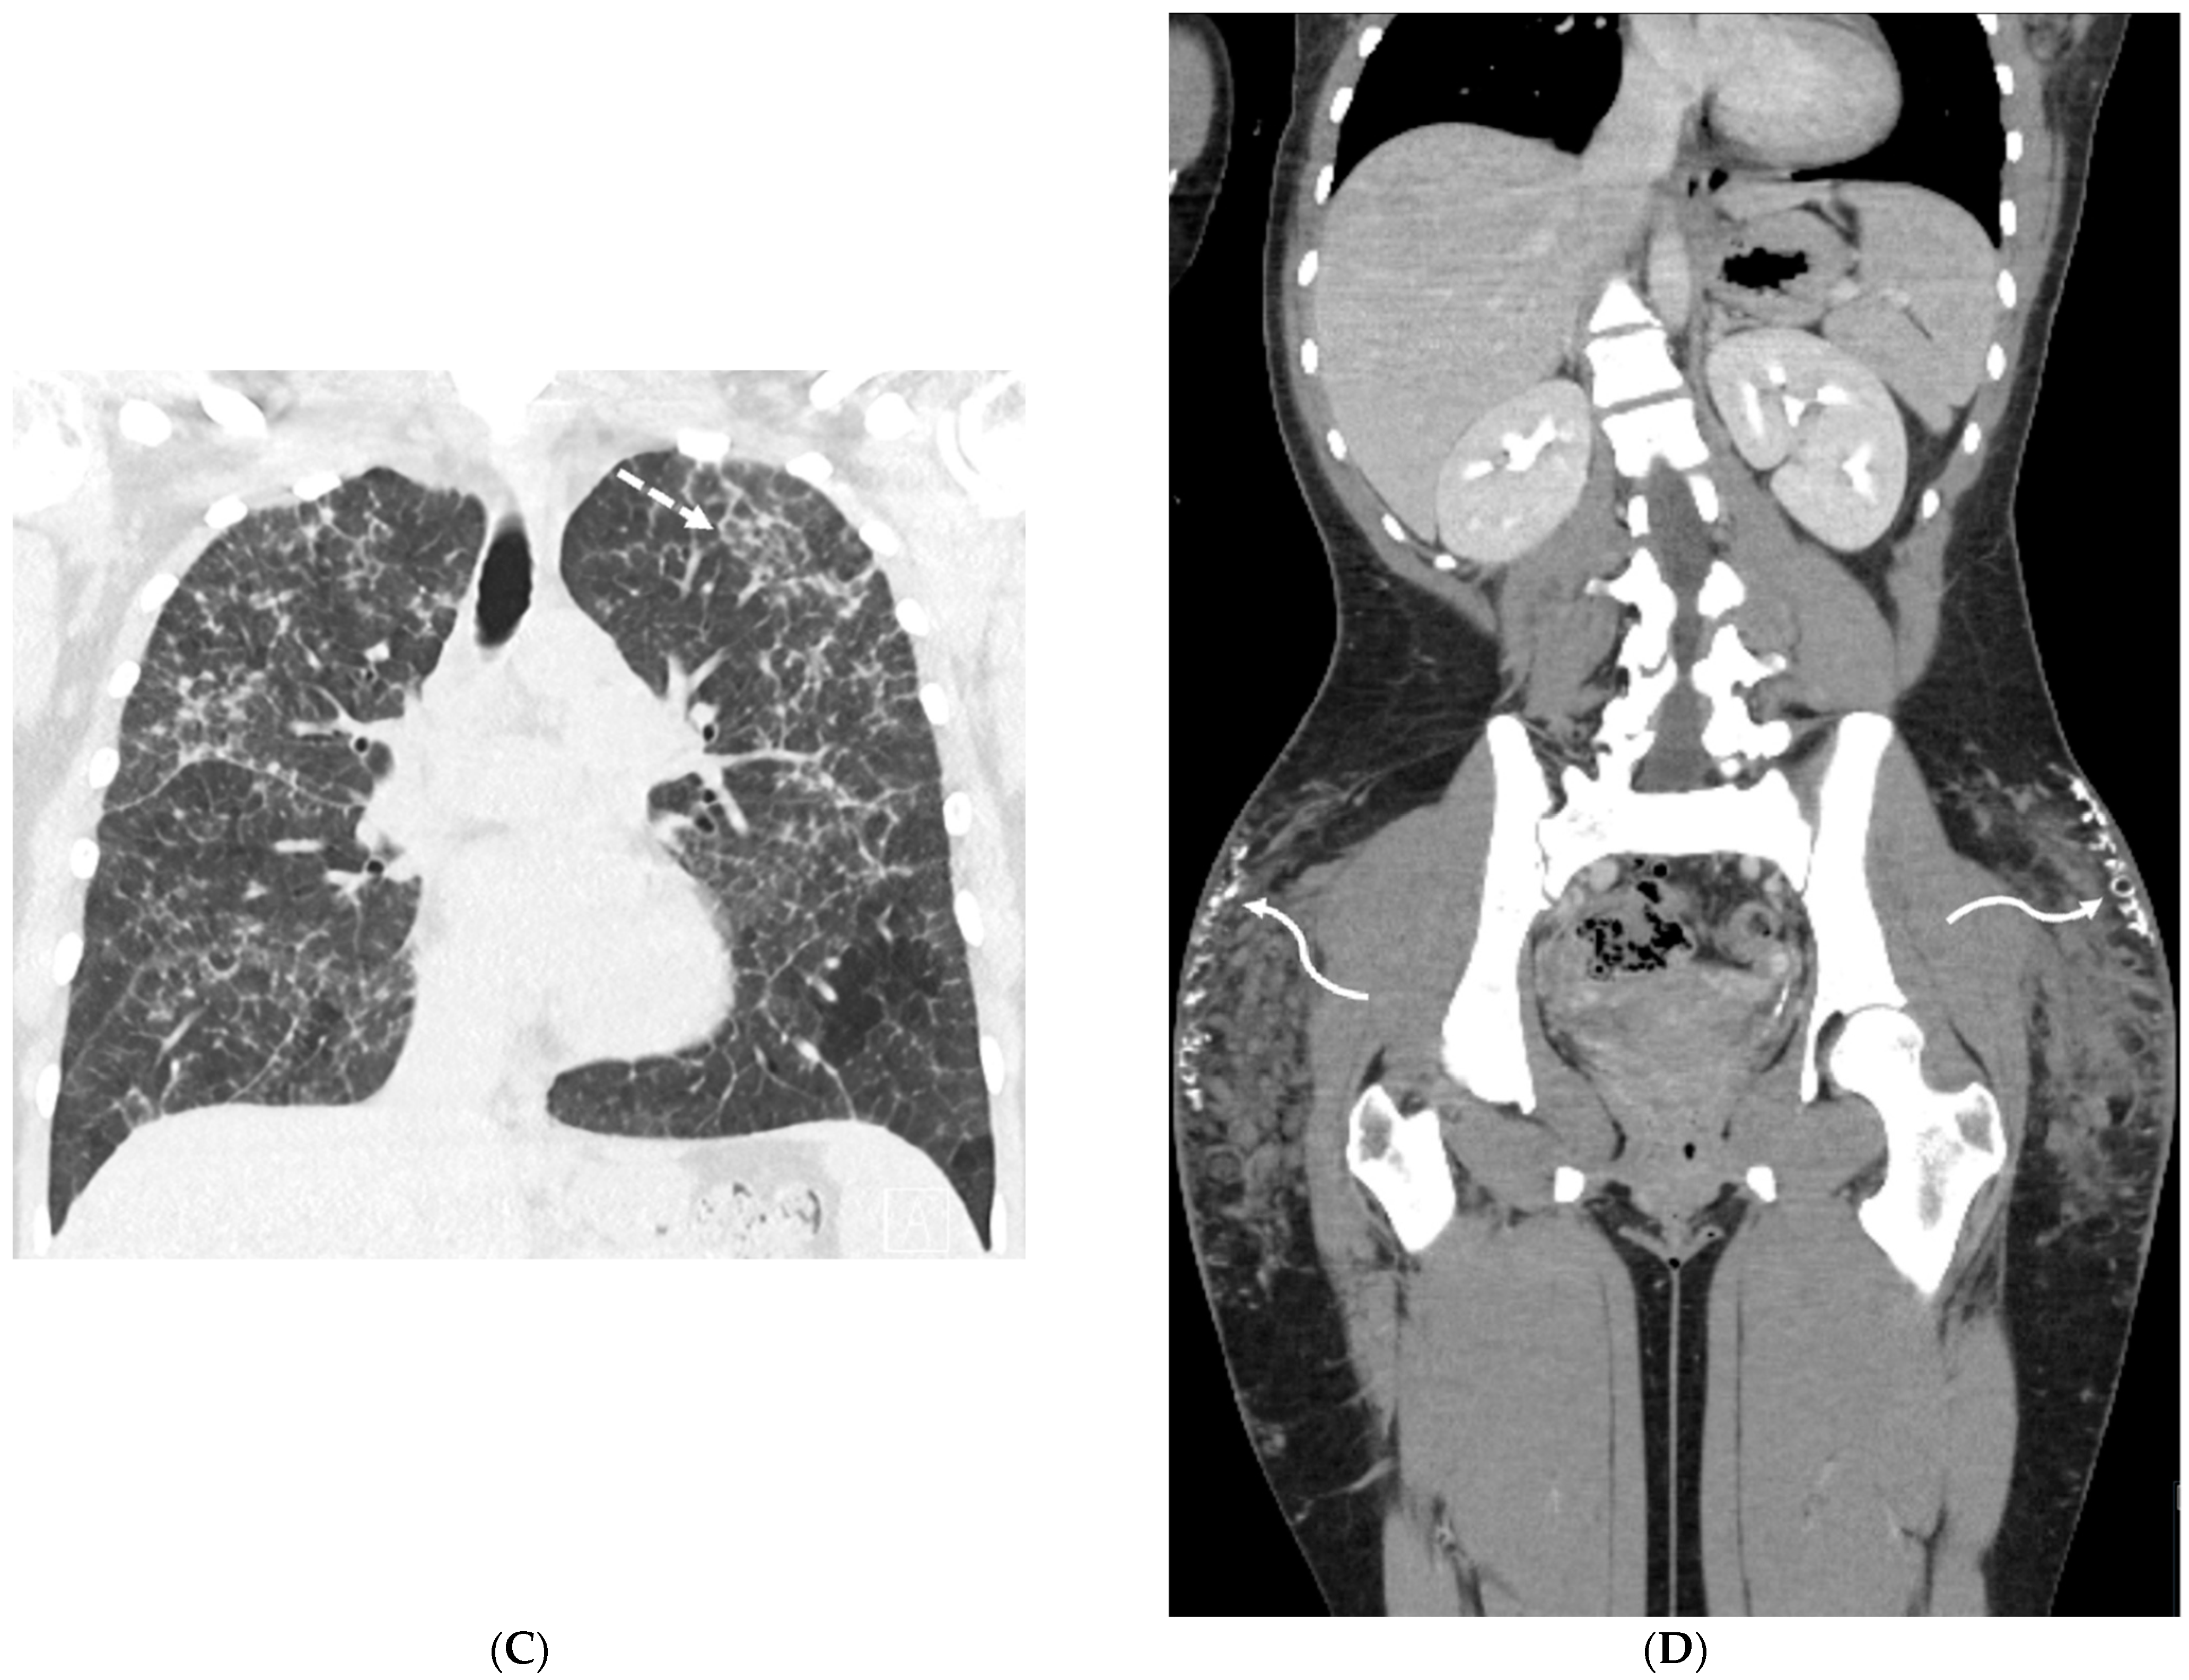

4.7. Pulmonary Vein Stenosis (PVS)

7.2. Pulmonary Capillary Hemangiomatosis (PCH) and Pulmonary Veno-Occlusive Disease (PVOD)